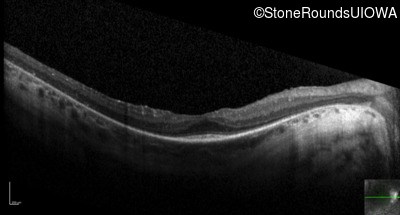

Optical Coherence Tomography - Right - 20/50

Exemplar / OCT Stack